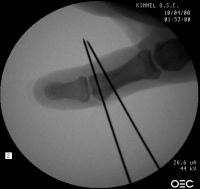

Osteotomy planning: proximal pin parallel to the proximal joint line, distal pin parallel to the distal joint line:

Click for larger image

Pins were used as saw blade alignment guides:

Osteotomy closed:

Intraosseous wire passed through pin tracts, interfragmentary pin: